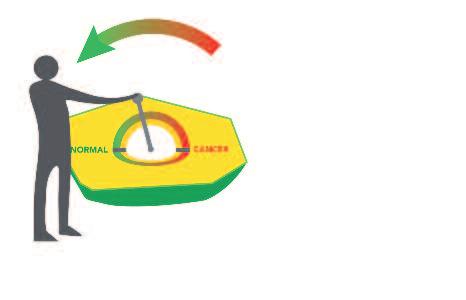

La ‘terapia’ convenzionale contro il cancro con il suo effetto deleterio per tutte le cellule sarà sostituita dal moderno metodo di 'regolazione cellulare'

Quindi, esiste un oggettivo bisogno di una metodologia completamente nuova nella terapia del cancro. Questo nuovo metodo deve essere basato su una nuova comprensione della regolazione naturale delle cellule tumorali. Il fattore chiave per il controllo efficace del cancro è rappresentato da determinate sostanze nutritive. Esse sono in grado di correggere il malfunzionamento del software biologico delle cellule tumorali, senza intaccare il metabolismo delle cellule sane. Con questi presupposti scientifici, il termine cancro non evocherà più il sentimento di paura che è solito accompagnare questo tipo di diagnosi.

Regolazione naturale implica

• Inibizione della crescita tumorale

• Inibizione delle crescita delle metastasi

• Incapsulamento dei tumori

• Eliminazione selettiva delle cellule tumorali

Il fattore chiave della vittoria sul cancro: Regolazione invece di intossicazione